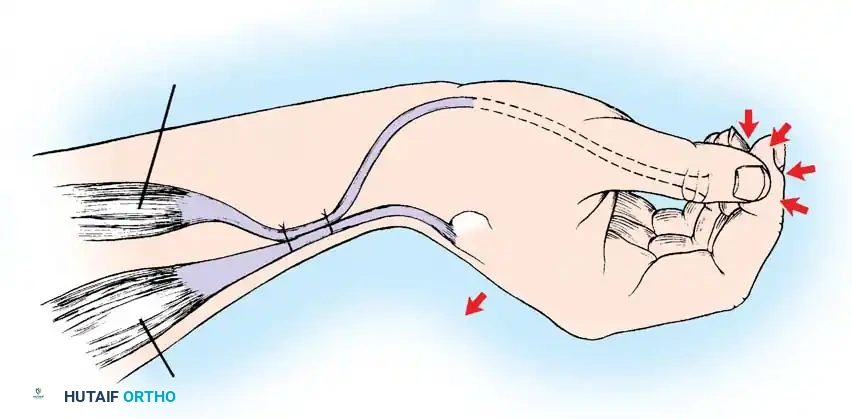

The Tenodesis Effect

In patients lacking active finger flexion, the natural tenodesis effect of the wrist must be harnessed. When the wrist is actively extended (via ECRL/ECRB), the extrinsic finger flexors (FDP, FDS) and the flexor pollicis longus (FPL) passively tighten, causing the fingers and thumb to flex and pinch against each other.

Moberg Key Grip Procedure

For Group 1 or Group 2 tetraplegics, the Moberg key grip procedure is foundational. This involves:

1. FPL Tenodesis: The FPL tendon is divided proximally and anchored to the distal radius. As the patient actively extends the wrist, the anchored FPL passively tightens, driving the thumb into lateral pinch against the index finger.

2. Thumb CMC Arthrodesis or Stabilization: To prevent the thumb from collapsing into retropulsion during pinch, the carpometacarpal (CMC) joint is often arthrodesed, or the metacarpophalangeal (MCP) joint is stabilized via capsulodesis or arthrodesis.

- Brachioradialis (BR) to FPL Transfer: The BR is an excellent donor for the FPL. It has immense power and adequate excursion. The BR must be mobilized extensively, proximal to the elbow joint, to maximize its amplitude.